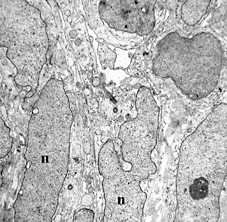

線維肉腫(低分化型)の電子顕微鏡像は紡錘形ないし一部類円形化した腫瘍細胞の増殖を示している。核は核縁の切れ込みが目立ち、明瞭な核小体を有している(図3矢印)。核クロマチンは核内(n)に均等に分布しており、細胞間には膠原線維が認められる(図4)。細胞膜は部分的に突起を示し、細胞内には一部、不規則に拡張した豊富な粗面小胞体がみられる。この粗面小胞体には無構造ないしは顆粒状物質を入れている。

図3 線維肉腫の電顕像 4000倍 図4 線維肉腫の電顕像 4800倍 図5 線維肉腫の電顕像 4800倍